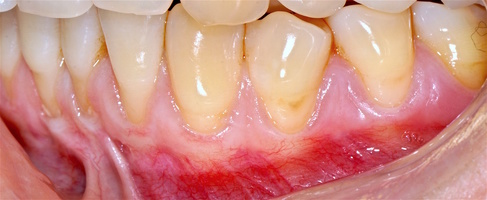

В марте 2017 года в клинику обратилась пациентка Ч., 28 лет (табл. 1) без вредных привычек, с положительным социальным статусом, астенического телосложения. С жалобами на тотальное обнажение корней зубов с повышением чувствительности от термических раздражителей, эстетические дефекты, абразии твердых тканей зубов.

Исходный объем мягкотканного комплекса атрофичен, тонкий биотип десны. Мелкое преддверие полости рта на нижней челюсти в переднем отделе, от 44-го до 34-го зубов высокое прикрепление слизисто-мышечных тяжей.

В области от 1.6 до 2.6 и от 3.6 до 4.6 все зубы имеют некариозные поражения разной степени, такие как эрозии эмали и клиновидные дефекты, вовлекающие в процесс ткани эмали и дентина. Подвижности зубов не выявлено (рис. 1а-е) [9].

Исходный диагноз: генерализованные рецессии десны 1 и 2 класса по Миллеру [7, 9, 10].